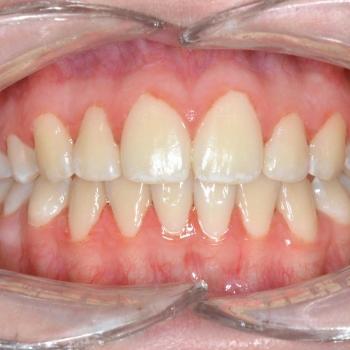

A kezelés megoldotta az összes fogszabályozással kapcsolatos problémát, így egy funkcionálisan és esztétikailag is megfelelő harapást kaptunk.

A kezelés teljes időtartama: 2 év